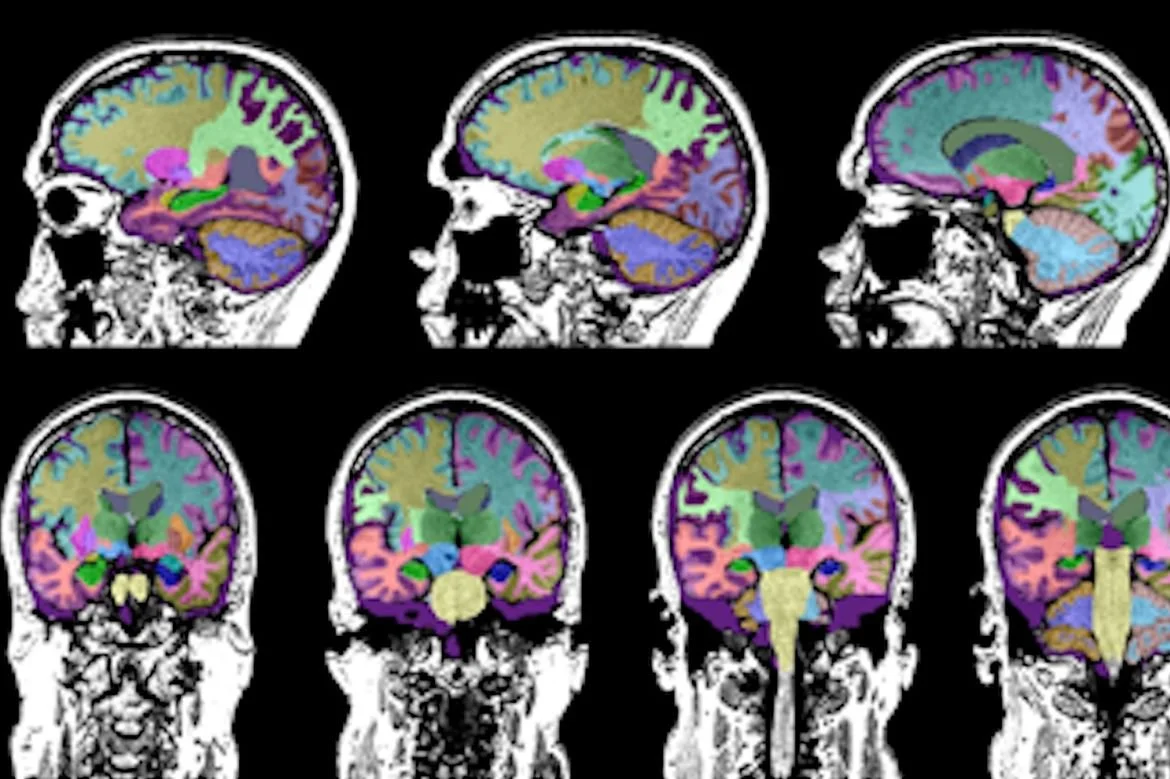

Our lab combines psychological assessment and state-of-the-art neuroimaging techniques (fMRI and PET) to advance understanding of the relationships between trauma (e.g. PTSD, borderline personality disorder, adverse childhood events) and risk for suicide. We aim to contribute to the development of precision psychiatric interventions, harnessing PET’s unique capacity to test brain and behavior relationships at a molecular level and novel techniques for analyzing behavioral health data. We further aim to contribute to the design and validation of psychiatric assessments to optimize measurement of trauma related psychopathology and constructs relevant to suicide behavior. Our underlying goal is to increase treatment options, create resources, and combat stigma in service of improving life for trauma survivors and the people who love them.

Dr. Davis is a licensed clinical psychologist and Associate Professor in the Yale Department of Psychiatry, co-appointed in the Department of Psychology. As an emergent expert in trauma-and-stressor related conditions, her work seeks to identify neurobiological mechanisms underlying behavioral responses related to PTSD, borderline personality disorder and other forms of trauma related psychopathology (e.g. eating disorders, OCD, substance use), and their link to suicide behaviors and functional impairment. Beyond her personal research projects, Maggie is a specialist with expertise and clinical experience in prolonged exposure, cognitive processing therapy, cognitive behavioral therapy (various protocols) and dialectical behavior therapy (DBT). She serves as the faculty lead for data integration and research management for the Yale New Haven Health Adult Behavioral Intensive Outpatient Program (IOP), Chair of the Scholarship Committee for the Yale Predoctoral Internship Program, and Director of BPD Outreach and Education for the Yale Department of Psychiatry.